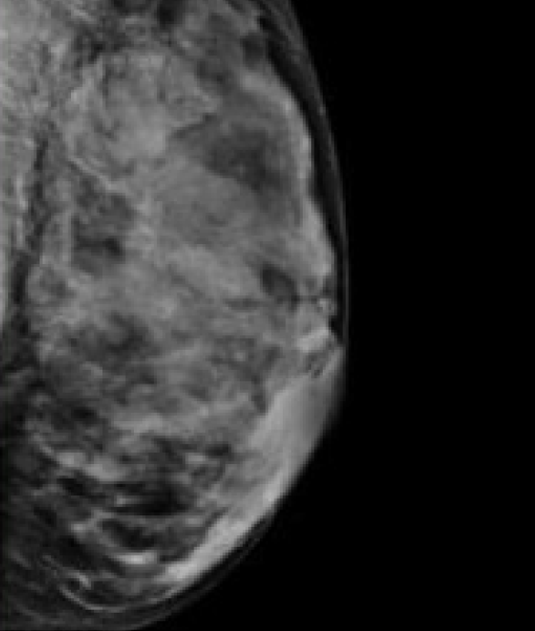

Previous Image Breast-Tissue-4 Breast is almost all glandular and fibrous. A small mass could be missed here.